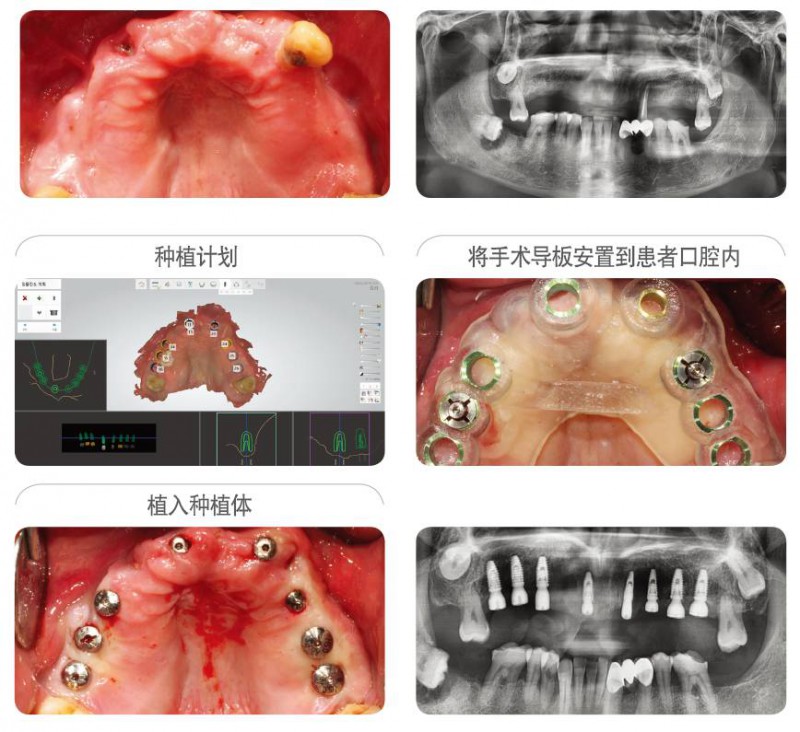

病例信息 : ST 牙科診所, 60s男性患者.

首次開展種植的牙科醫(yī)生為自己家人施術(shù)的案例.利用紐白特?cái)?shù)字化手術(shù)導(dǎo)板簡單的植入8顆種植體,使得在顧問醫(yī)生的幫助下制定的治療計(jì)劃,完美的再現(xiàn)在患者口腔內(nèi)。